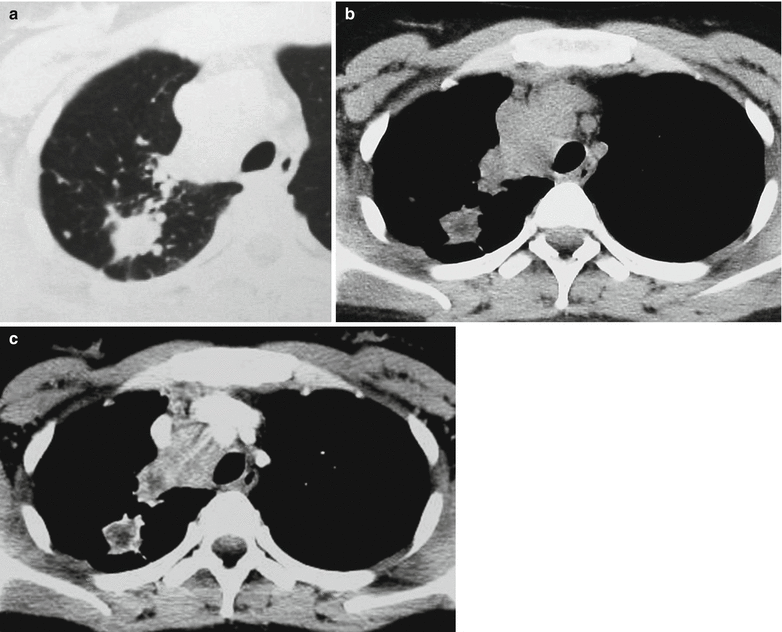

Tuberculosis CT Chest Review Old Tb Radiology Therefore, time from acquisition of infection to the development of clinical disease does not reliably predict the radiographic appearance of tb. Prior sarcoid prior exposure to silica dust Unfortunately, a history of infection with or exposure to tuberculosis may or may not be present, and evidence of active tuberculosis is present in less than 50% of cases. Sequelae of previous. Old Tb Radiology.

Pulmonary Tuberculosis Radiology Key Old Tb Radiology The list of possible causes include: Persons who have nodular or fibrotic lesions consistent with findings of old tuberculosis on chest radiograph and a positive tuberculin skin test. Stability of radiographic findings for 6 months distinguishes inactive from active disease. In fact, the advances in molecular epidemiology in the 1990s have led to the discovery that the radiographic appearances of. Old Tb Radiology.

Tuberculosis A Radiologic Review RadioGraphics Old Tb Radiology Therefore, time from acquisition of infection to the development of clinical disease does not reliably predict the radiographic appearance of tb. Sequelae of previous tuberculosis that is now inactive manifest characteristically as fibronodular opacities in the apical and upper lung zones. The list of possible causes include: Tb dna has been isolated from bone marrow, and it seems possible that. Old Tb Radiology.